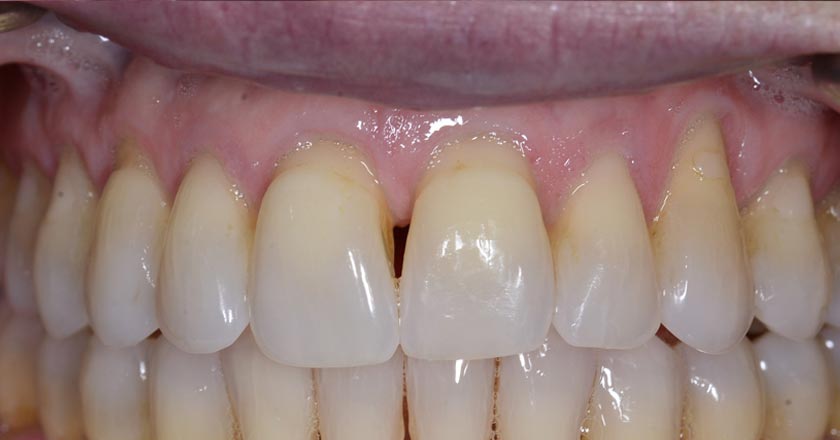

Gum Graft Upper - Before And After

Gum graft upper – before treatment

Gum graft upper – after treatment